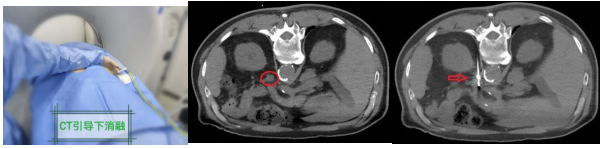

方式:腹腔镜下切除病变侧肾上腺或腺瘤。(近年来,我国学者也探索性地进行介入治疗方法,积累了宝贵的临床经验,比如肾上腺热消融、肾上腺动脉栓塞等)

(醛固酮腺瘤介入热消融治疗)